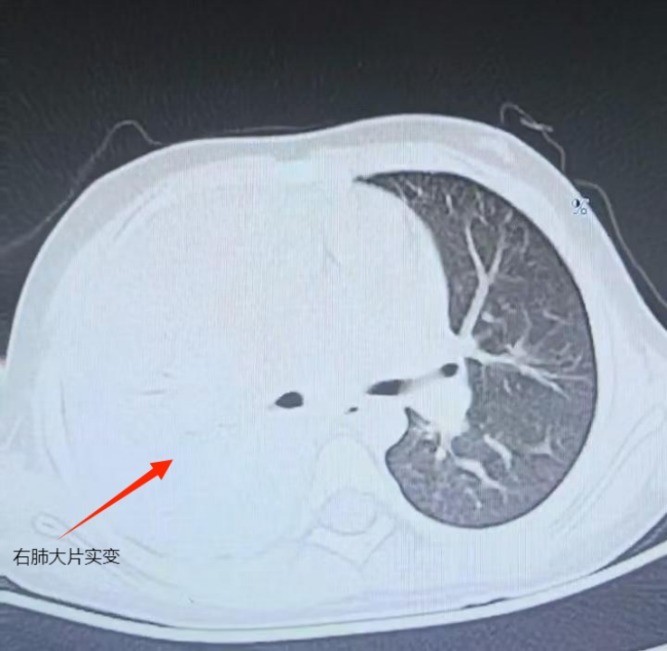

r据了解,家长小宇在当地医院完善胸部CT检查发现“右肺大面积炎症伴肺不张”,随即住院治疗,连续静脉输注“阿奇霉素+头孢类”抗生素7天,仍未见好转。

r住院时孩子已经出现胸痛、呼吸急促,咳血性黏痰,经进一步检查,右肺已进展为“坏死性肺炎”,增强CT影像显示右肺多发蜂窝状空洞,病情危殆。